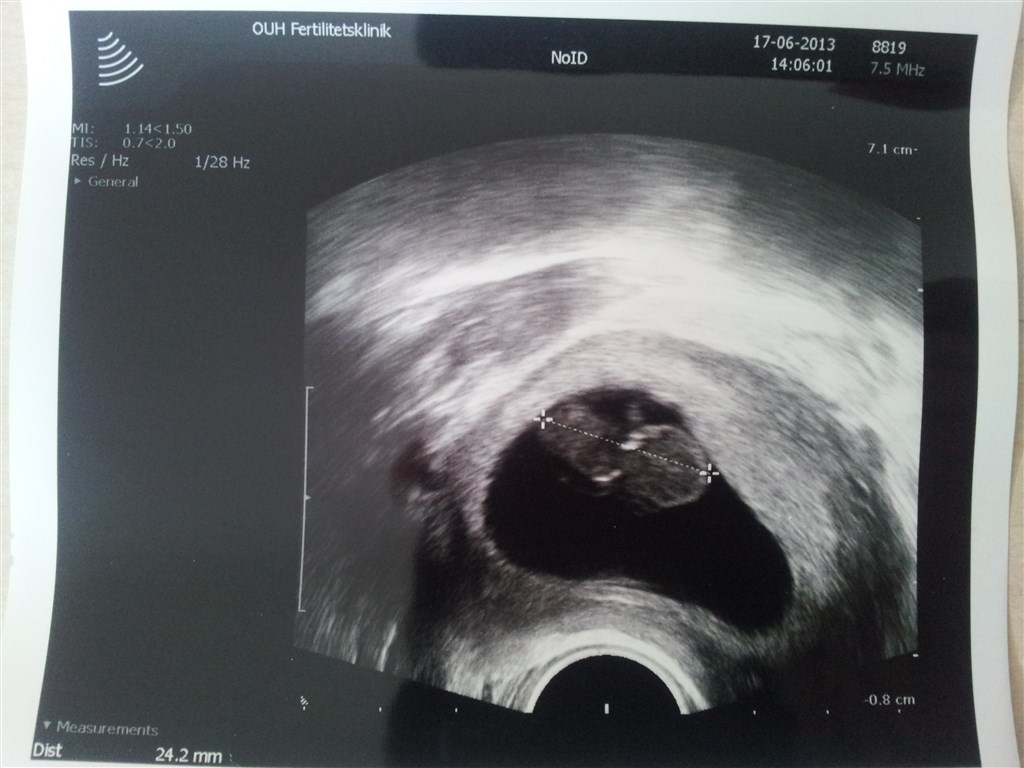

Også et billede af tvilling 2, som måler 24.2 mm.

Man kan jo sagtens se en forskel på de to og til trods for der var hjerteblink hos dem begge i uge 8+0 og tvilling 2 var 2 mm kortere end tvilling 1 - lader det til at den er gået til..